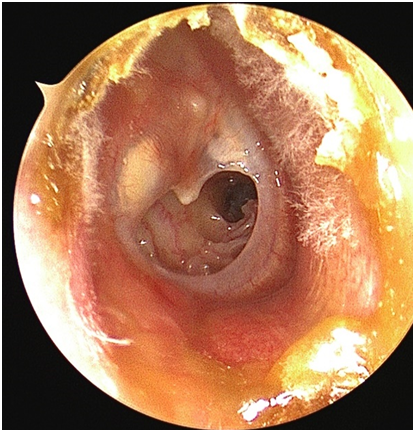

图为患者鼓膜穿孔照片

患者为40岁藏族男性,患有中耳炎达数年,该患者因反复耳流脓伴听力下降数十年曾多次就诊于当地医院,予以相应治疗,但流脓、听力下降的症状在感冒或耳朵进水等刺激后会有所加重,因对疾病的认识不足及医疗条件的限制,致使病史长达数十年。

慢性化脓性中耳炎是指中耳黏膜、骨膜或深达骨质的慢性化脓性炎症。本病是临床上的常见病,西藏等高原地区尤其多发。慢性化脓性中耳炎常以耳内间断或持续性流脓、鼓膜穿孔、听力下降、耳鸣为主要临床表现,严重时可引起颅内、颅外的并发症。